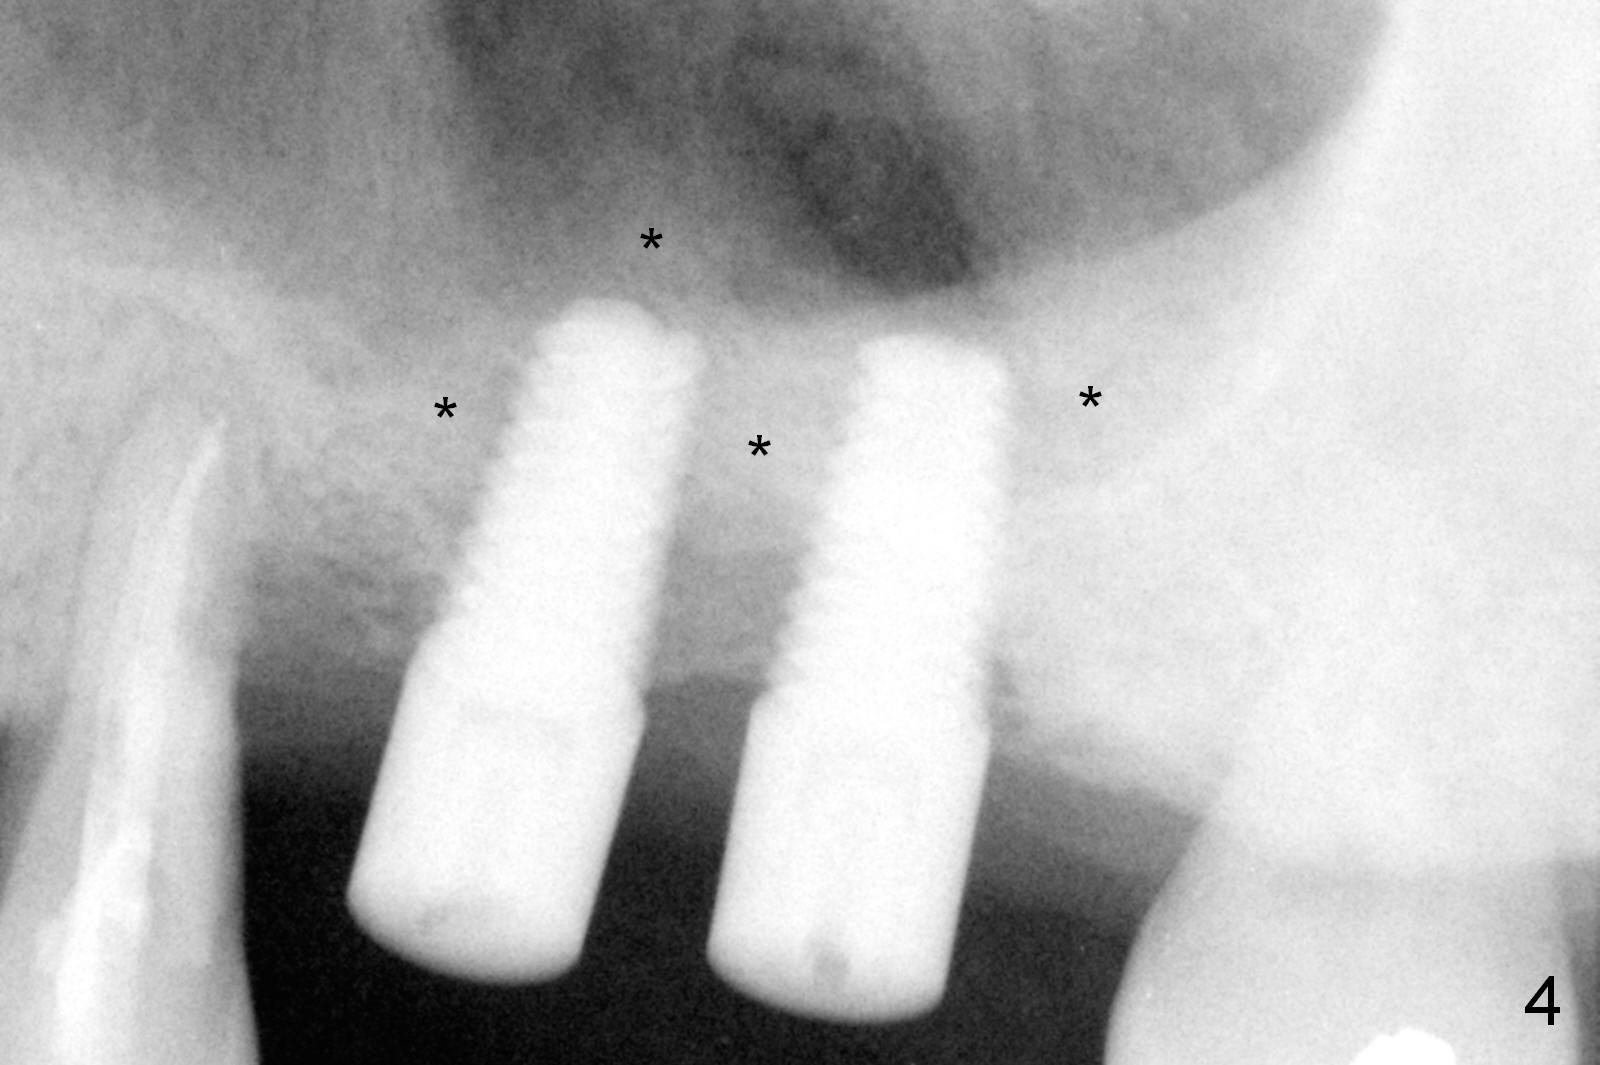

Mild to moderate hemorrhage is encountered as soon as incision is made for the lateral window. It is a concern prior to bone graft and implant placement. Hemorrhage appears to come from the sinus. Bleeding may wash away the graft. Therefore several pieces of Collagen Dressing are inserted into the sinus for hemostasis, followed by placement of Osteogen (Fig.1 *) and implant (5x14 mm, tissue-level). After placement of the 2nd implant, more Osteogen is placed buccal to the implants. Insertion torque is ~ 35 Ncm. Abutments (Fig. 2: 4x5 mm) are placed to hold perio dressing in place (no immediate provisional). In fact, the patient returns within 20 minutes postop because hemorrhage from the incision. Hemostasis is achieved with a few pieces of gauze in the buccal vestibule. Ice pack is recommended. By the evening, the patient reports minimal oozing. When perio dressing is lost 10 days postop, the wound opens (Fig.3). Later the wound heals. It appears that an immediate provisional provides the wound with temporary protection. The abutments without provisional is irritating to the soft tissue (the cheek in this instance). They have to be removed until the implants osteointegrate. PA taken 4 months postop shows the bone in the sinus surrounding the implants (Fig.4 *). The gingiva around the implants looks normal (Fig.5), although there is occasional and mild itching in the skin over the left sinus.

Approximately 2 months post cementation, the patient complains of looseness of one of the implants. It is probably due to the fact that the sinus floor is too thin (2-3 mm), that the Tatum implant threads do not fully engage into the native bone (the rough portion) and that the implant is loaded too soon. If the implant turns out to be minimally loose, remove the crown and the unipost and place a healing screw. If the implant is fatally loose, remove it, explorer the osteotomy for wall integrity. If it is solid, place 5.5 or 6.0 mm tap before placing an appropriate implant and healing abutment for more than 6 months (vs. 4 months previously). In fact, the implant is quite loose with bone loss around the implant.